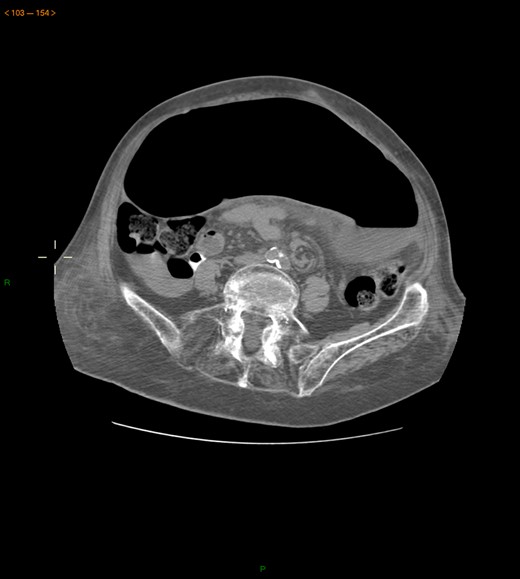

Case 2: A 92-year-old women, without previous abdominal surgery or history of abdominal trauma or peritoneal infections was admitted to the emergency department with generalized abdominal pain. Physical exam revealed markedly distended abdomen with generalized abdominal pain with tenderness. Laboratory investigation on admission: white cell count of 30.200/mm3 with 84.7% neutrophils, protein C reactive of 13.6 mg/dL and lactates of 2.17 mmol/l. Abdominal X-ray showed a marked colonic enlargement. Abdominal-pelvic CT identified a colonic volvulus associated with a transmesocolic hernia with transmural necrosis of the colon sigmoid (Figs 2 and 3). The patient was proposed to laparotomy during which a volvulus of colon sigmoid with transmural necrosis in a strangulated transverse transmesocolic and transomental (great omentum) hernia was identified (Figs 4 and 5). A Hartmann procedure was conducted and the patient was discharged at fifth post-operative day. At 3 months follow-up consultation, the patient remained free of complains.

Abdominal-pelvic CT—transverse plane: colonic volvulus associated with a transmesocolic hernia with transmural necrosis of the colon sigmoid.